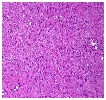

AbstractLeiomyoma is a benign soft tissue neoplasm originating from smooth muscles. While leiomyomas most frequently occur in the uterine myometrium (95%), they are also found in the skin (3%), gastrointestinal system (1.5%), and in less than 1% of cases in the head and neck region . The tumor generally appears in the 4th and 5th decades of life, more commonly in females, and typically presents as a slow-growing, asymptomatic lesion.The main treatment for leiomyoma is surgical resection, and recurrence is quite rare. In this case report, we present a rare case of a giant solid leiomyoma located in the supraclavicular region, which we evaluated clinically, histopathologically, and radiologically IntroductionLeiomyoma is a benign neoplasm arising from smooth muscle cells and is most commonly found in the uterus, skin, and gastrointestinal tract. However, due to the limited presence of smooth muscle tissue in the head and neck region, leiomyomas in this area are extremely rare, accounting for less than 1% of all cases. These tumors generally present as slow-growing, painless masses and are more frequently observed in middle-aged women. Histopathologically, leiomyomas consist of bundles of well-differentiated spindle cells with eosinophilic cytoplasm and show strong immunoreactivity for smooth muscle markers such as smooth muscle actin (SMA), desmin, and caldesmon. Based on histological features, leiomyomas are classified as solid leiomyoma, vascular leiomyoma (angioleiomyoma), and epithelioid leiomyoma. Although their pathogenesis remains unclear, theories suggest that they may originate from the vascular smooth muscle of small blood vessels or pluripotent mesenchymal cells. Surgical excision remains the mainstay of treatment, and recurrence is uncommon. In this report, we present a rare case of a giant solid leiomyoma located in the supraclavicular region, evaluated clinically, radiologically, and histopathologically. Case ReportA 33-year-old male presented to the Otorhinolaryngology Department of Antalya Training and Research Hospital with a complaint of swelling in the left supraclavicular region for six months, which had gradually increased in size. On physical examination, a firm, fixed, smooth-surfaced, tender mass approximately 7x5 cm in size was palpated in the left supraclavicular area. Neck ultrasound revealed a heterogeneous hypoechoic mass lesion originating from muscle tissue on the left lateral neck measuring 78x68x36 mm. MRI of the neck showed a mass lesion located posteriorly in the left supraclavicular region with a maximum size of 91x58 mm, hyperintense on T2-weighted images, and intensely enhanced after intravenous contrast administration (Figure 1). Fine-needle aspiration (FNA) biposy was and diagnosis of a benign spindle cell benign tumor was made.

Histopathological examination confirmed the diagnosis of leiomyoma (Figure 3).

DiscussionA systematic approach and treatment plan should be followed for differential diagnosis of supraclavicular masses. Inflammatory events and benign lesions are more common in young adults, while malignancies are more likely in patients over 40. Our patient was under 40 years of age and had a benign lesion, leiomyoma. Leiomyomas are most commonly seen in the uterine myometrium (95%), followed by the skin (3%), gastrointestinal tract (1.5%), and less than 1% in the head and neck region [1]. Our case was particularly rare due to its supraclavicular location. Detailed patient history and physical examination are crucial for diagnosis. Conditions such as prior diseases, trauma history, and accompanying symptoms should be questioned. Physical exam should assess mass mobility, firmness, and presence of bruits. Systemic examination is essential, as many masses in this region are secondary findings. In our case, the mass was immobile with no bruits, and the patient had a trauma history but no known chronic diseases. Leiomyomas often contain calcifications and their clinical appearance is usually an asymptomatic, slowly growing mass [5]. However, in our case, the mass grew rapidly within 6 months. It can be challenging to distinguish leiomyoma from leiomyosarcoma preoperatively, and indeed in our case there was suspicion of invasion of the surrounding muscle tissue and scapula on preoperative imaging, but this suspicion was reduced when the FNA biopsy was reported as benign. Histologically, the tumor showed eosinophilic spindle cells, consistent with literature. Immunohistochemical staining was positive for SMA and calponin, and the Ki-67 index was <1%, also consistent with existing data. Proposed mechanisms for leiomyoma development include congenital origin, vascular abnormalities, infection, and estrogen involvement, although no consensus exists. Progesterone receptors have also been shown to be expressed in tumor cell nuclei, possibly explaining higher prevalence in females [6]. Although trauma is not usually involved in etiology, the mass developed after a trauma he experienced four years ago. Although FNA biopsy may be difficult due to calcification, we believe that this procedure may be the first choice to differentiate benign from malignant leiomyoma in the neck. ConclusionIn conclusion, we present a rare case of giant leiomyoma in the supraclavicular fossa. This case report emphasizes that leiomyoma should be considered as a differential diagnosis when investigating patients with a lateral neck mass. References